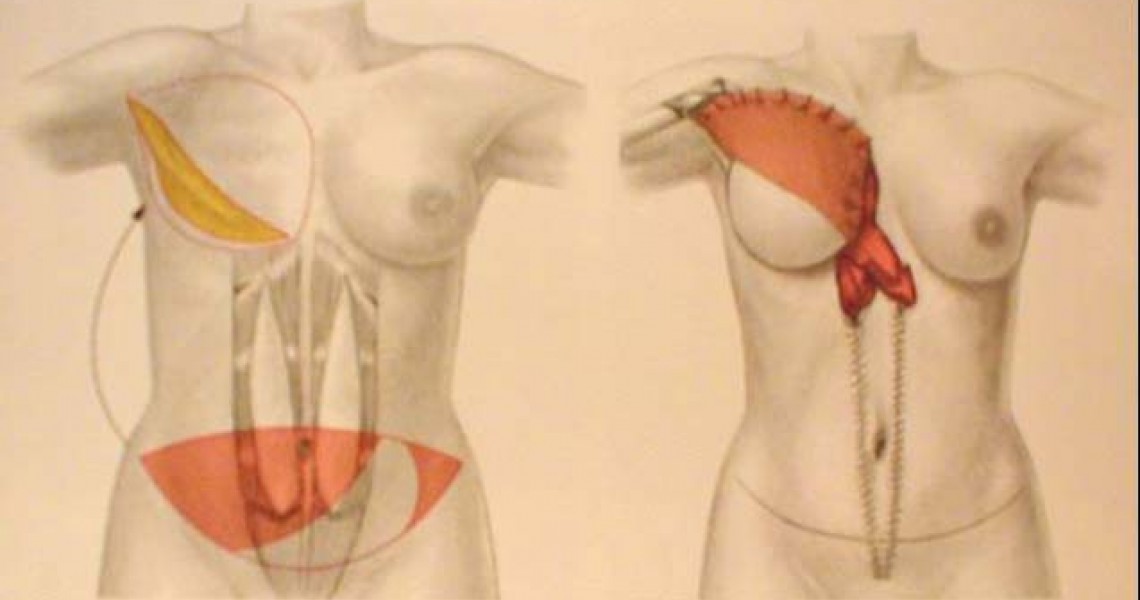

Αληθινό στήθος στην αποκατάσταση

«Αληθινό μαστό- RealBreast» με αυτολόγο μόσχευμα-κρημνό-(ιστός -δέρμα και λίποςμαζί με τα αγγεία του) αποκτά πλέον η πλειοψηφία των γυναικών που κάνει αποκατάσταση στήθους μετά από μαστεκτομή, χάρις στην εξέλιξη της μικροχειρουργικής!

«Το αποτέλεσμα είναι εντυπωσιακό καθώς ο νέος μαστός που δημιουργείται από ιστό της γυναίκας...